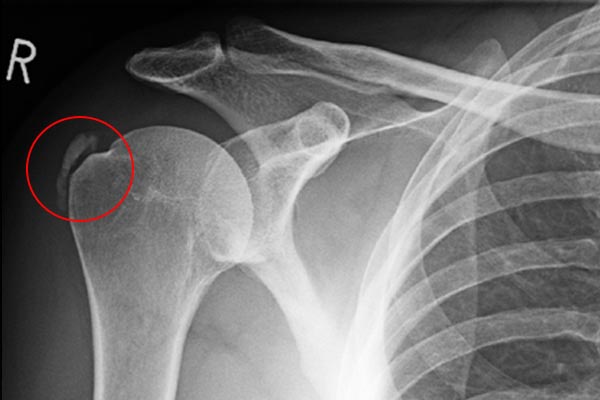

Svi su čuli za kalcifikat (pijesak) u ramenenu kojega radiolog otkrije preko rendgen snimke, te potom svi stručnjaci taj isti kalcifikat optuže za sami uzrok boli. U većini slučajeva zaključak je pogrešan, jer kalcifikat je najčešće asimptomatičan!

Slika 1 pokazuje kalcifikat na tetivi supraspinatusa (najčešće kalcifikat nije uzrok boli)